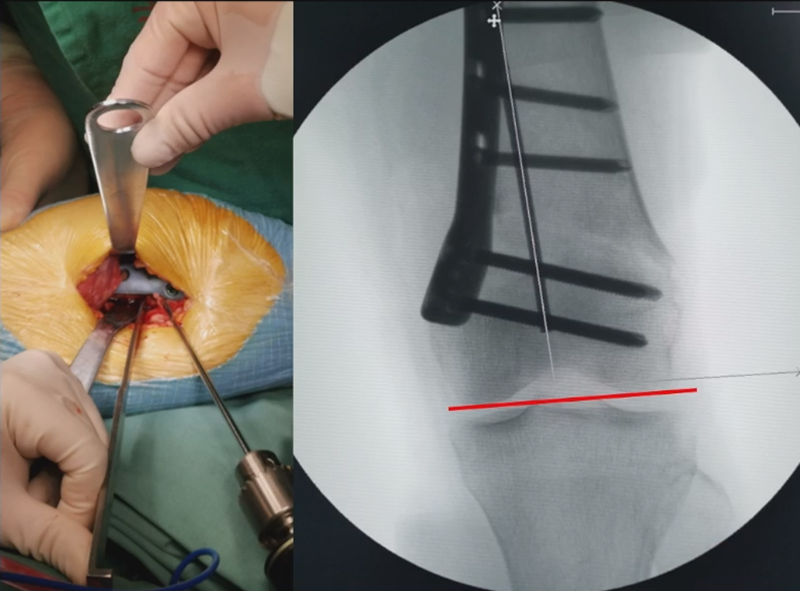

术中发现螺钉松动,截骨端出现坎插迹象。

近端螺钉松开,调整力线,重新固定后,在外侧加小钢板抗旋。